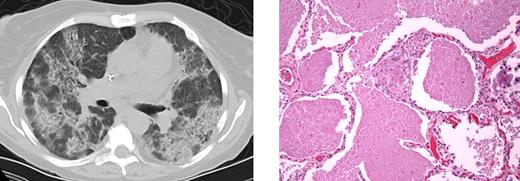

PAP (Figure 2) developed in 6 patients (4 female, 2 male) with a median age of onset of 42 years (range, 25-60 years). Autoantibodies to GM-CSF were not detected, nor were mutations in the GM-CSF receptor α chain or common β chain. Neither subcutaneous nor aerosolized GM-CSF had significant effect. Periodic whole-lung lavages were moderately effective.

PAP in patient 3.I.1. Computed tomography (left) demonstrates significant bilateral airspace disease. Histopathology (right) demonstrates excessive accumulation of amorphous proteinaceous material in the alveolar spaces. Images were taken using an Olympus Bx41 microscope, objectives UPlanFI 40×/0.75 ∞/0.17, and UPlanFI 20×/05.0 ∞/0.17, with an adaptor U-TV0.5×C using a digital camera Q-imaging Micropublisher 5.0RTV. The images were captured using Q-Capture Version 3.1 and imported into Adobe Photoshop 7.0.